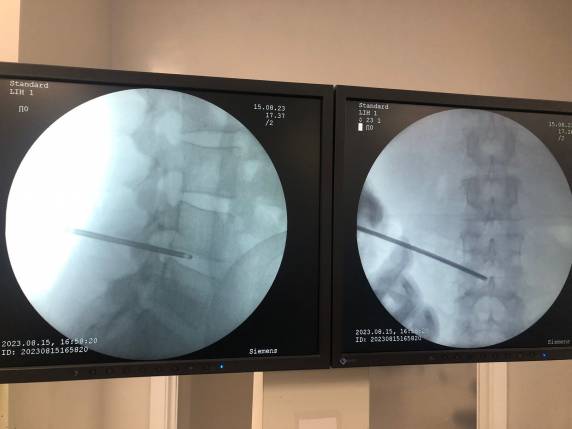

A realização de procedimentos minimamente invasivos é uma tendência que cresce cada vez mais. E até mesmo patologias mais comuns podem ser tratadas através de cirurgias realizadas por vídeo, como é o caso da hérnia de disco. Recentemente, foi realizado no Centro Cirúrgico do Hospital Vida & Saúde, uma cirurgia percutânea de hérnia – a primeira deste tipo realizada no município.

Realizada a partir de uma pequena incisão, sem necessidade de abertura cirúrgica da coluna. Especialista em cirurgia de coluna, o médico Vanderlei Sartor explica que a cirurgia percutânea de hérnia é indicada de acordo com a gravidade de cada caso. Diferentemente da cirurgia convencional, este tipo de procedimento possibilita uma recuperação mais rápida. “É um procedimento de alta resolutividade, com pouco sangramento e que possibilita uma alta precoce e a volta mais rápida às atividades de rotina do paciente”, destaca.

Em procedimentos convencionais, o paciente passa por um processo mais invasivo, que ocasiona em uma internação hospitalar mais prolongada. No caso da cirurgia realizada no HVS, o paciente recebeu alta oito horas após a cirurgia.